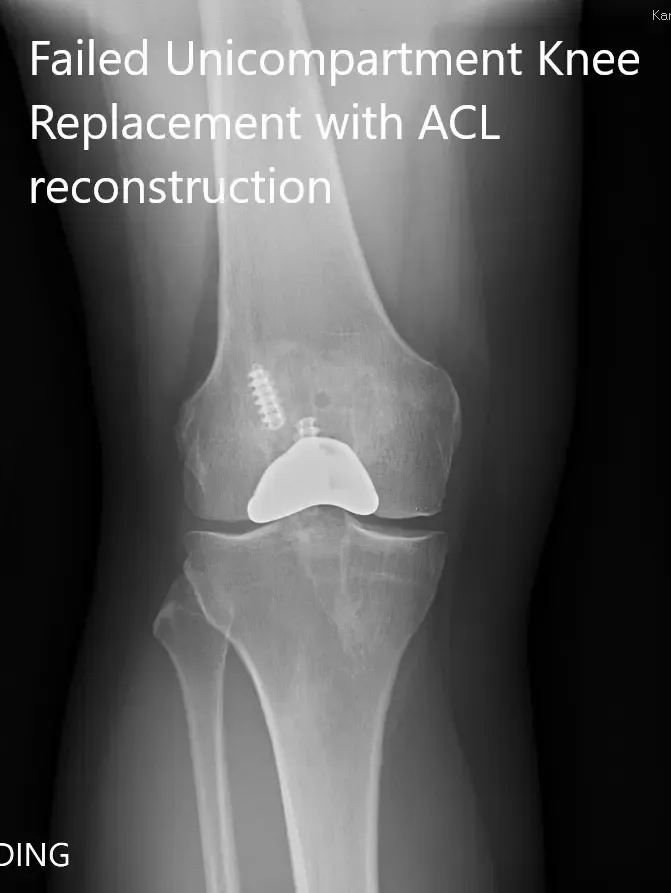

Preoperative x-ray showing the anteroposterior and lateral views of the right knee

PREOPERATIVE DIAGNOSIS(ES): Failed Right knee unicondylar knee replacement.